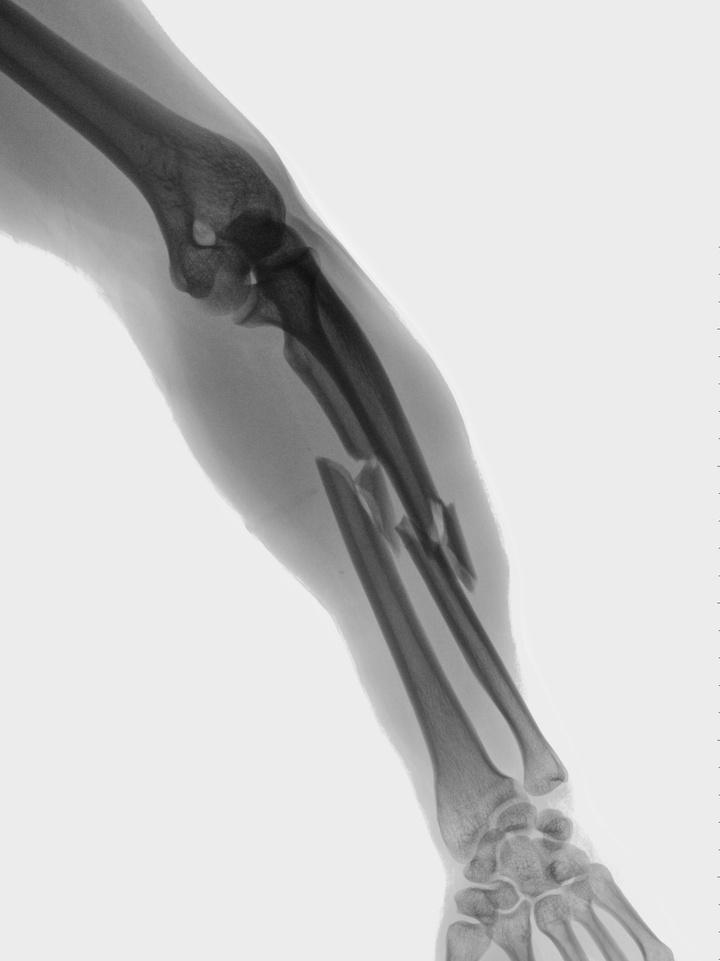

In osteoporosis, both your bone density and bone quality are reduced which will increase your risk of fracture. Why is this important?

Approximately 10 million Americans have osteoporosis, and another 44 million have low bone density. One in two women and up to one in four men will break a bone in their lifetime due to osteoporosis. For women, the incidence is greater than that of heart attack, stroke, and breast cancer combined.

Six months after a hip fracture, only 15 percent of patients can walk across a room unaided.

Every year, of nearly 300,000 hip fracture patients, one-quarter end up in nursing homes, and half never regain previous function.